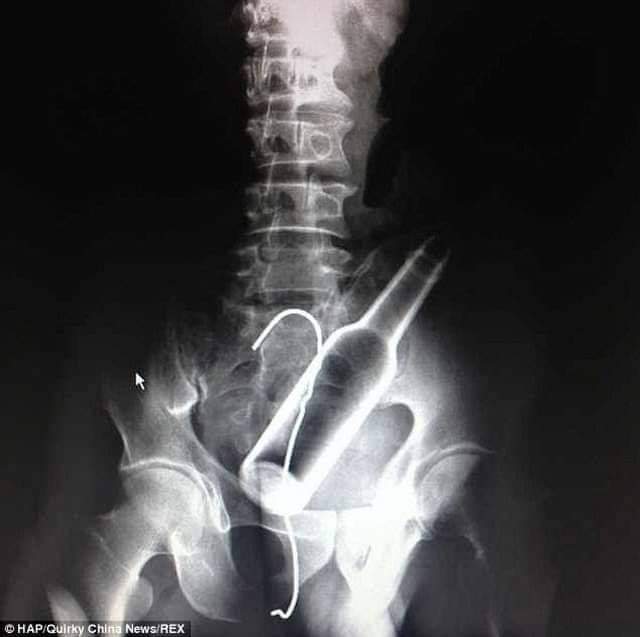

Un extranjero de habla inglesa de aproximadamente 50 años, llego a la unidad de urgencias del Hospital Julio Méndez Barreneche con una botella de cerveza dentro de su recto, tras un aparente ‘juego sexual’.

No obstante, llegadas las 7:00 de la mañana el extranjero regresó al área de urgencia, esta vez contando que tenía una botella de cerveza en el ano, que, según su propio relato, su esposa se la introdujo para cumplir un deseo sexual cuando estos tenían relaciones, pero el recto del extranjero se inflamó y la botella de vidrio quedó adentro sin que la pudieran sacar.

Una fuente médica menciono que, «la operación quirúrgica duró menos de 30 minutos, mientras relajaron el músculo en forma de anillo que abre y cierra la abertura del ano y con unas pinzas extrajeron el cuerpo extraño. La cirugía fue de alto riesgo, pues los galenos temían hacer un vacío con la botella y que se estallara dentro del recto». Finalmente, el hombre fue dado de alta con medicación para el dolor .